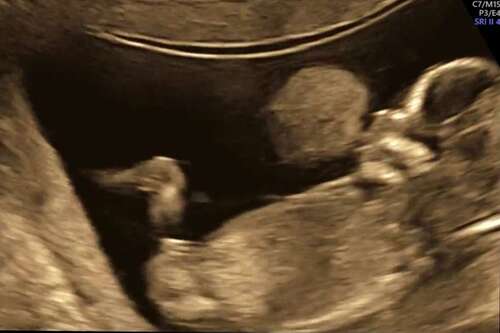

13+1 weken

Deze is gisteren gemaakt tijdens de 13 weken echo.

Ik ben super benieuwd 💗💙

Hier is de nub dus niet goed te zien. Meer het been = dus niet door het midden.

(Blaas wel mooi in beeld ;-))